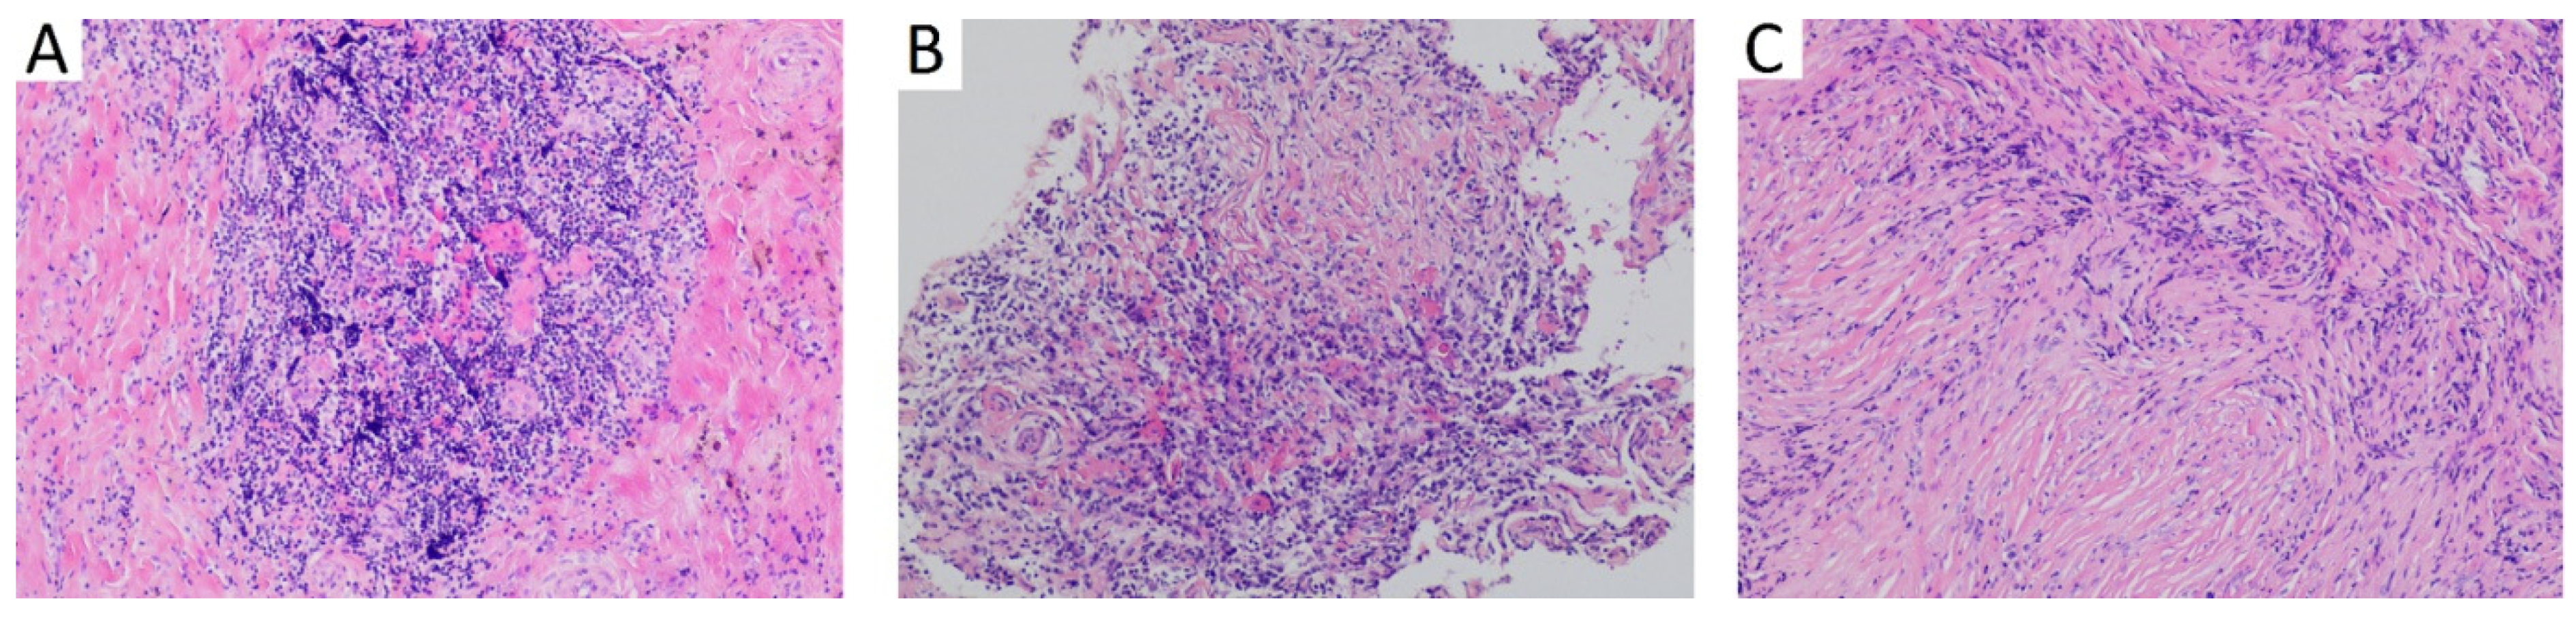

| 18 | 2016 | Israel | Present study | 48 | m | otitis media with effusion | 1 | - | fibrous tissue with storiform fibrosis, lymphoplasmacytic infiltration, obliterative phlebitis | IgG4 positive 15 per HPF; IgG4:IgG < 20% | 210 mg/dL |

| 19 | 2021 | Israel | Present study | 44 | m | otitis media | 1 | - | fibrous tissue, dense lymphoplasmacytic inflammation, storiform fibrosis | IgG4 25 per HPF; IgG4:IgG < 20% | Data not available |